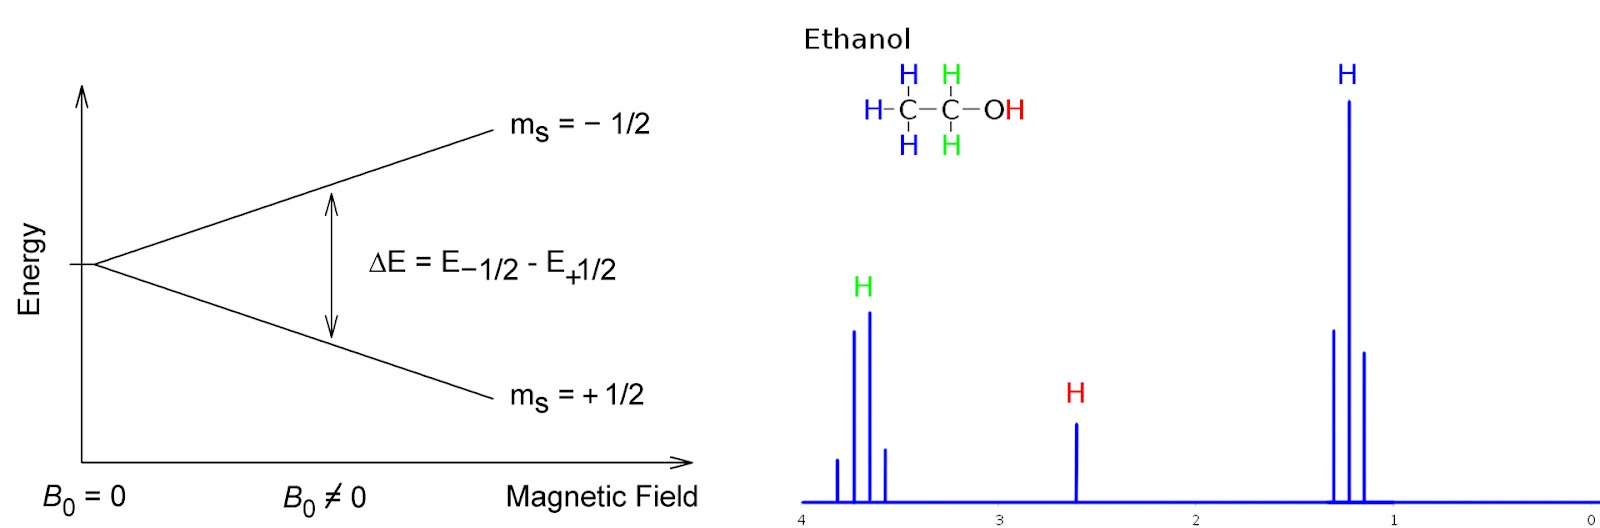

Метод МРТ основан на явлении так называемого ядерного магнитного резонанса. Очень кратко и грубо можно объяснить это явление следующим образом. Существуют атомы, ядра которых обладают спином, кратным ½. Подобные ядра имеют магнитный дипольный момент, и могут взаимодействовать с внешним магнитным полем (правда, поле должно быть достаточно сильным, чтобы это взаимодействие можно было детектировать). При наложении внешнего магнитного поля на образец вещества происходит расщепление на два энергетических уровня, соответствующих состояниям +1/2 и -1/2 с различными энергиями (разность энергий зависит от силы приложенного поля):

Дальше – дело техники: в квантовом мире все устроено так, что разности энергий должна соответствовать какая-либо электромагнитная волна определенной частоты. Необходимо подобрать эту внешнюю частоту (в приборах ЯМР-анализа это радиодиапазон), либо наоборот, менять силу магнитного поля, пока разность энергий не совпадет с заданной в приборе частотой. Собственно, все – для надежности и повышения качества сигнала он записывается множество раз, улучшая соотношение сигнала к шуму.

Химики используют ядра водорода, а также специально введенные в состав молекулы изотопы углерода-13, фтора-19, чтобы изучать этим методом структуру веществ. Дело в том, что помимо собственного сигнала, ядра взаимодействуют друг с другом, давая множественный сигнал (см. рисунок). Именно благодаря этой картине ученые могут установить взаимное расположение функциональных групп атомов – так изучают структуру неизвестных молекул, или подтверждают наличие/отсутствие побочных продуктов в химической реакции.